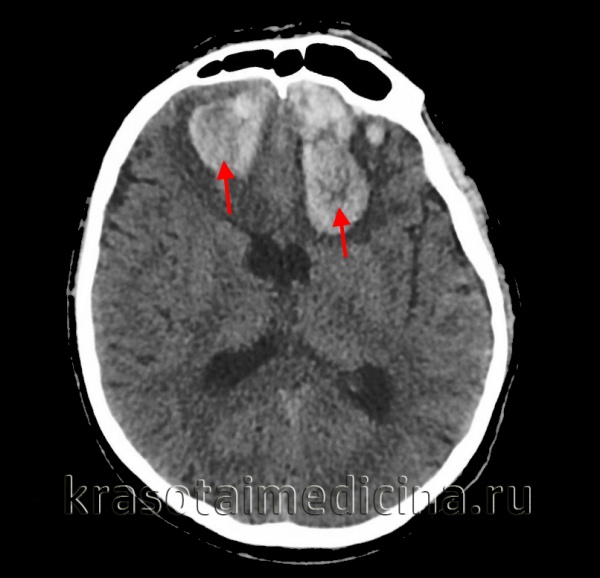

(а) Макропрепарат головного мозга, сагиттальный срез: определяются признаки полного двустороннего нисходящего транстенториального вклинения головного мозга. Зрительный перекрест и III желудочек деформированы турецким седлом. Также выявляются смещение среднего мозга книзу и уменьшение угла между ним и мостом

(б) MPT, выполненное непосредственно перед смертью, MP-RAGE Т1 -ВИ, сагиттальный срез: у пациента с полным центральным вклинением головного мозга определяется нисходящая дислокация среднего мозга, моста и миндалин мозжечка.